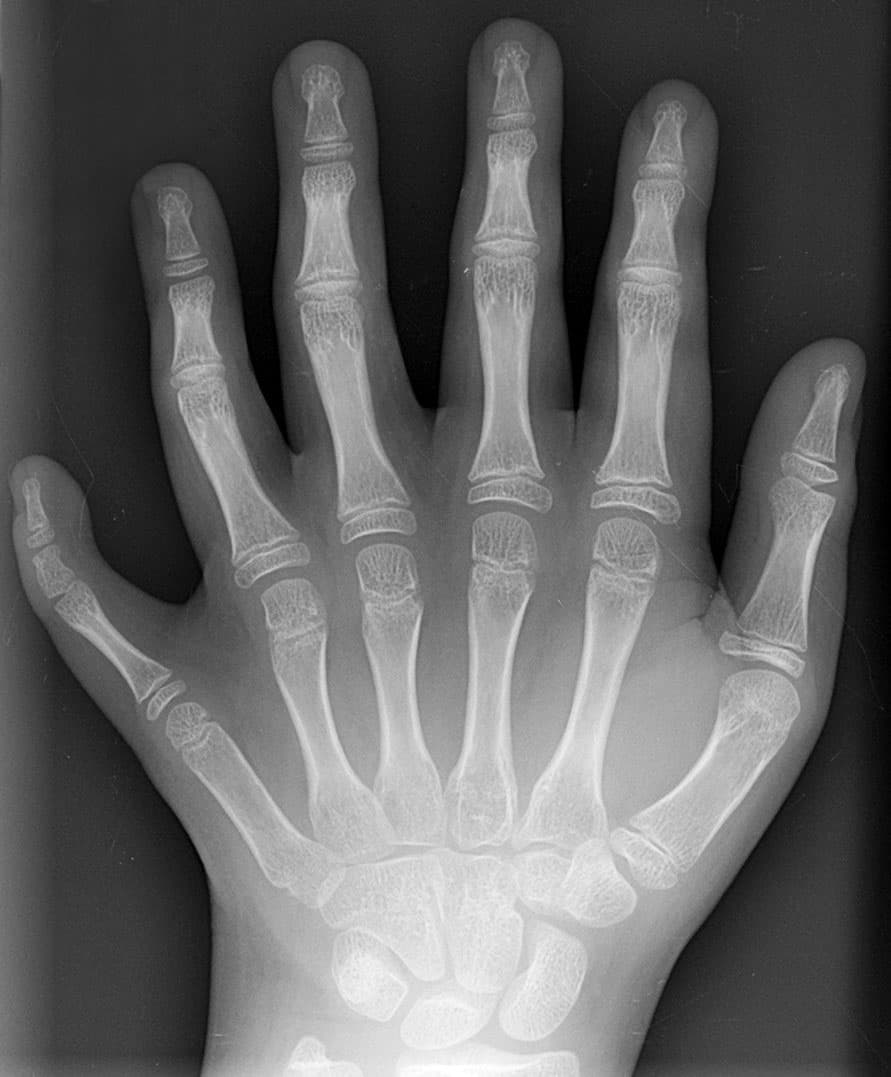

La polydactylie (du grec « poly » : « nombreux » et « dactyle » : « doigts ») se définit comme la présence d’un ou plusieurs doigts supplémentaire(s) au niveau de la main ou d’un ou plusieurs orteils au niveau du pied. Les gènes induisant le développement de la polydactylie sont toujours présents chez les formes actuelles, ce qui suggère que dans l'histoire évolutive du vivant, la polydactylie apparaît comme la condition plésiomorphe pour les tétrapodes, c'est-à-dire la condition primitive initiale du membre marcheur, la pentadactylie n'étant pas la disposition « canonique » de la structure de ce membre marcheur. Cette malformation connue depuis longtemps est décrite dans la Bible. La polydactylie de la main est la plus fréquente des malformations de la main, l'hexadactylie (6 doigts ou orteils) la plus fréquente des polydactylies ( pour mille naissances). On distingue classiquement la polydactylie « préaxiale » de la polydactylie « postaxiale », bien que certains contestent cette classification. La polydactylie est une caractéristique de plusieurs maladies chromosomiques ou génétiques. Elle fait souvent suite à une mutation du gène HoxD 13 entrainant une mauvaise apparition de l'autopod. Définie comme l’existence des doigts supplémentaires du côté de l'ulna ou d’orteils du côté de la fibula (donc du côté du petit doigt). Elle peut être complète : présence d'un doigt bien formé ou plus rudimentaire. Elle est plus fréquente, et moins spécifique que la polydactylie préaxiale. D'après une étude américaine, la polydactylie postaxiale isolée est plus fréquente chez la population noire (1 pour 100) et se transmettrait sur un mode dominant. Elle atteint plus souvent les hommes que les femmes. Dans de rares cas, il peut y avoir présence simultanée de 12 doigts et 12 orteils. Un cas exceptionnel d'enfant naissant avec 14 doigts et 20 orteils, né en 2010, a été découvert en Inde. Cinq ans plus tôt, un enfant chinois était né avec 15 doigts et 16 orteils.